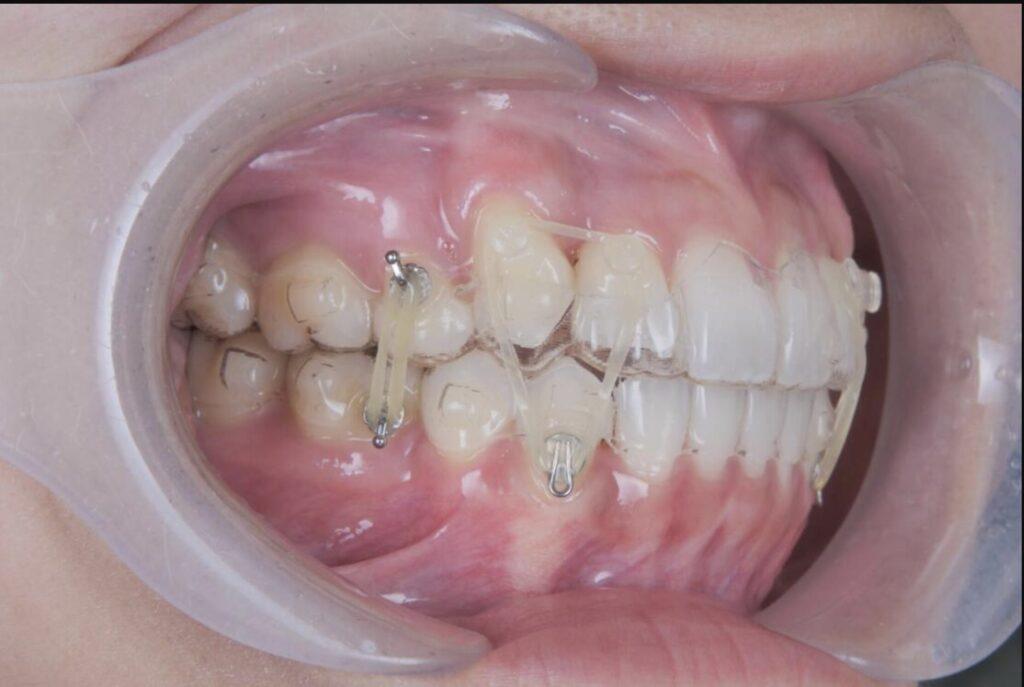

例えばこの患者様もマウスピース矯正中に歯茎が腫れてしまいましたが、適切に対応することで、現在では問題なく治療が進んでいます。当院では、そのようなトラブルがあってもラインにて対応ができるので、安心とおっしゃっていただく患者様が多いです。

食べ物がつまり、上記の部分が腫れて痛みがあり、マウスピースの装着が困難な状態でしたが、清掃指導及びマウスピースの辺縁を調整することで、治療の中断することなく、矯正治療を進めることができました。その後、患者様もフロスや歯間ブラシを使っていただくことで、良好に経過しています。